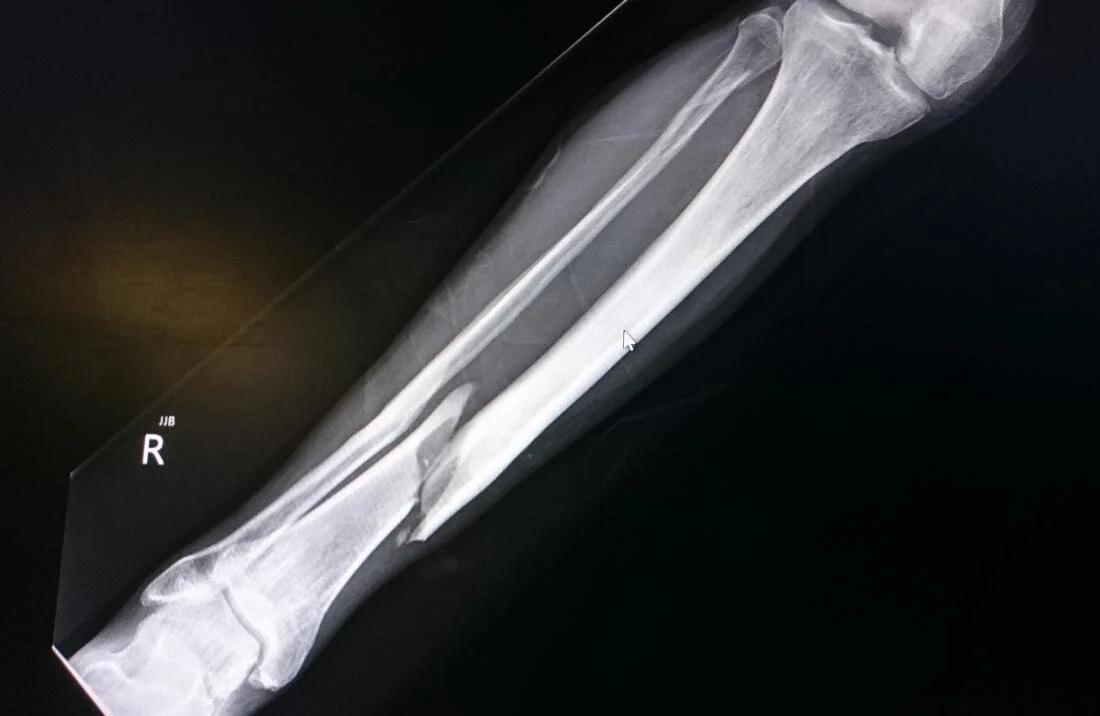

Interesting Orthopaedics

Presentation is here